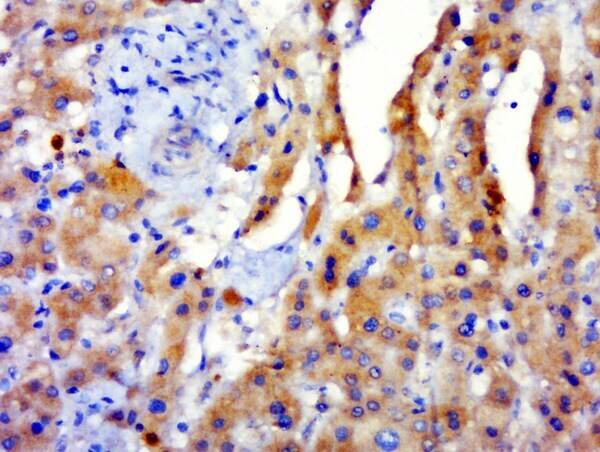

Supportive validation

- Submitted by

- Invitrogen Antibodies (provider)

- Main image

- Experimental details

- Paraformaldehyde-fixed, paraffin embedded human hepatocellular carcinoma tissue; Antigen retrieval by boiling in sodium citrate buffer(pH6) for 15min; Block endogenous peroxidase by 3% hydrogen peroxide for 30 minutes; Blocking buffer (normal goat serum) at 37°C for 20min; Antibody incubation with Rabbit Anti-GPATCH3 Polyclonal Antibody, Unconjugated (bs-13500R) at 1:500 overnight at 4°C, followed by a conjugated secondary and DAB staining.